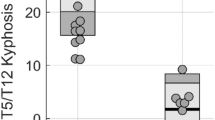

In the group S, after kaolin-induction, the VDmax and VUmax of CSF flow at the levels of C0 and C7 were diseased gradually. Especially, at week 12, being compared with the preoperative state, the VDmaxs at the level of C0 and C7 were decreased to 3.9 ± 1.0 cm/sec (P ≤ 0.001) and 4.2 ± 1.0 cm/sec (P ≤ 0.001) obviously, and the VUmaxs were also decreased to 4.4 ± 1.2 cm/sec (P ≤ 0.001) and 4.6 ± 0.9 cm/sec (P ≤ 0.001). Meanwhile, the spinal curve was observed initially from week 6, then the cobb angle of scoliosis was increased to 27.4 ± 10° at week 12 (Fig. 4).

Moreover, in order to analyze the relationship between CSF flow changes and scoliosis formation, a correlational analysis was performed for all rabbits in group S at postoperative 12 weeks, and the results indicated a remarkable correlation of the final Cobb angle of scoliosis and the ∆VDmax (the decrease of VDmax from preoperative state to postoperative 12 weeks) and ∆VUmax (the decrease of VUmax from preoperative status to postoperative 12 weeks). At C0 and C7 levels, both ∆VDmax and ∆VUmax were positively correlated to the final scoliotic Cobb angle (P < 0.01) (Fig. 5).

Relationship of CSF flow change and scoliosis formation at postoperative 12 weeks. ∆VDmax and Cobb angle at level of C0. Pearson correlation analysis shows a significant positive correlation of ∆VDmax versus Cobb angle (Pearson r = 0.595; P ≤ 0.001, n = 27). Line represents linear regression of data (y = 7.265x+ 4.808; r2 = 0.3542) (A). ∆VUmax and Cobb angle at level of C0. Pearson correlation analysis shows a significant positive correlation of ∆VUmax versus Cobb angle (Pearson r = 0.673; P ≤ 0.001, n = 27). Line represents linear regression of data (y = 7.240x+ 4.140; r2 = 0.4523) (B). ∆VDmax and Cobb angle at level of C7. Pearson correlation analysis shows a significant positive correlation of ∆VDmax versus Cobb angle (Pearson r = 0.668; P ≤ 0.001, n = 27). Line represents linear regression of data (y = 7.636x+ 3.103; r2 = 0.4460) (C). ∆VUmax and Cobb angle at level of C7. Pearson correlation analysis shows a significant positive correlation of ∆VUmax versus Cobb angle (Pearson r = 0.683; P ≤ 0.001, n = 27). Line represents linear regression of data (y = 8.588x+2.716; r2 = 0.4662) (D).